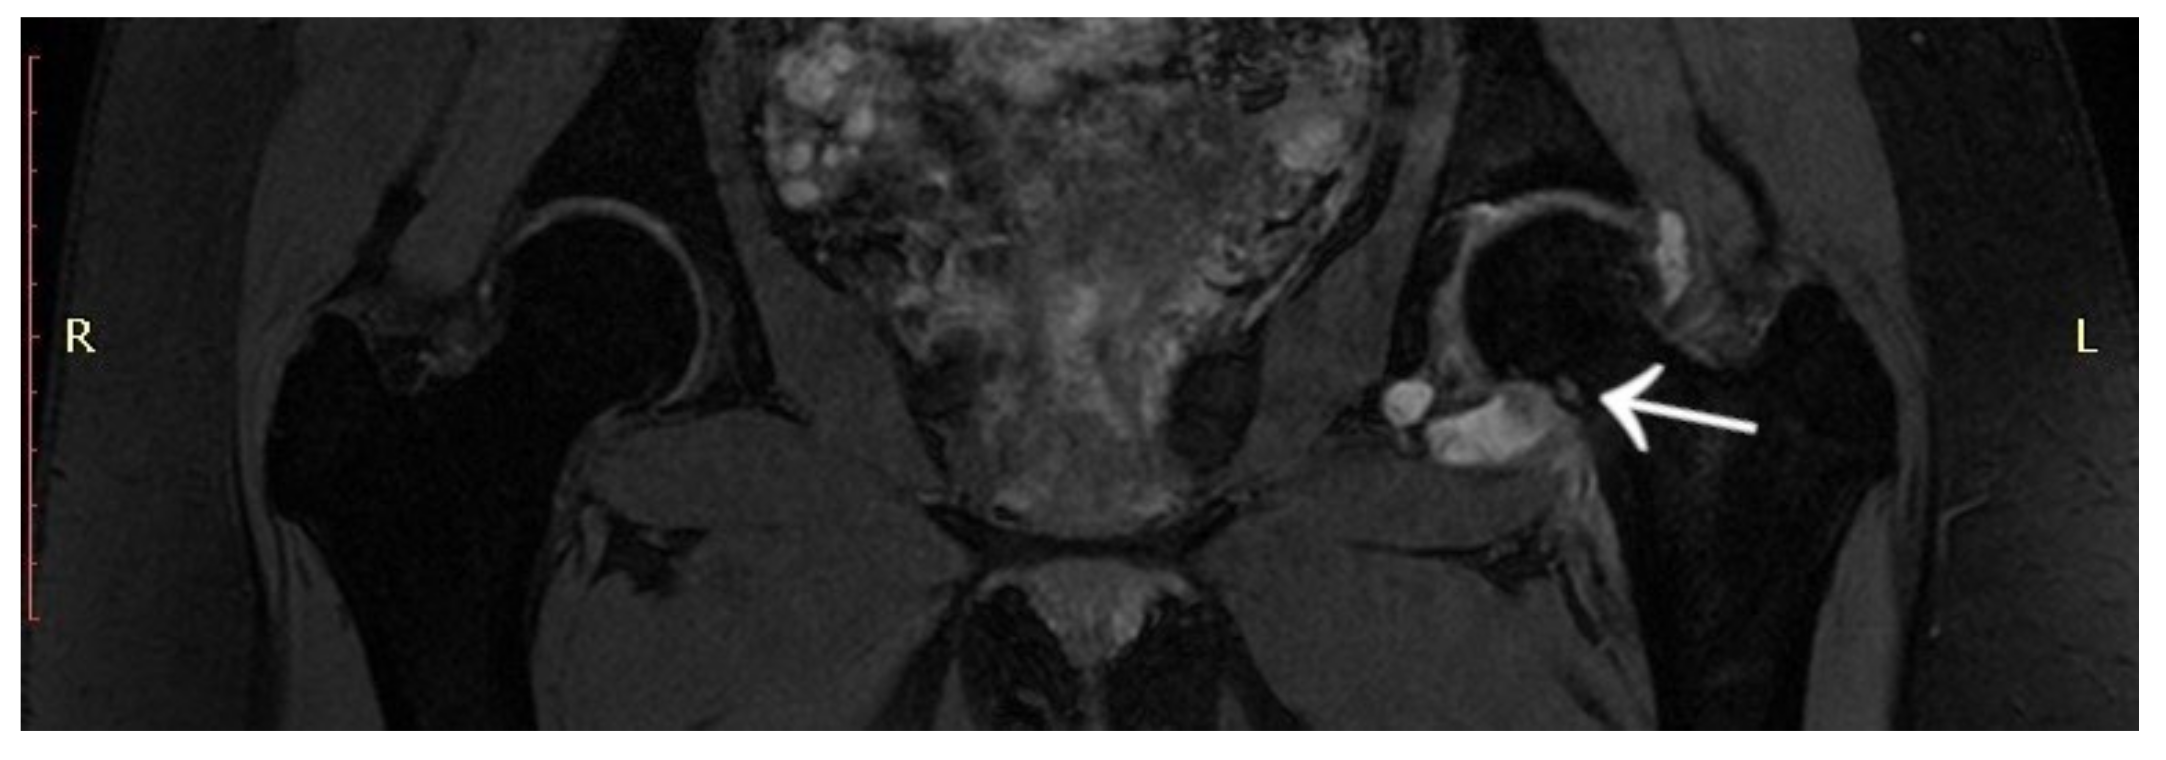

A 6-year-old girl was admitted to the Research Hospital of Orthopaedics for Children and Adolescents with symptoms of night pain (VAS score of 7), especially in the left knee, with lesser intensity in the left hip, accompanied by limping and decreased appetite. The diagnosis made six months earlier detected leucocytosis (23,000), positive IgM antibodies, and Western blot for Lyme disease. A diagnosis of Lyme disease was made, and the patient was treated with antibiotic therapy. The symptoms did not resolve after treatment. The patient underwent an MRI scan of the hip joints (Figure 5). Based on that examination, the patient was diagnosed with a left femoral neck stress lesion with a secondary fracture. The patient also underwent bone scintigraphy, showing a lesion in the left femoral neck (Figure 6). Persistent leucocytosis with the stimulation of granulocytes and features of abnormal cell maturation prompted a double bone marrow trephine biopsy and femoral biopsy. The image of the bone marrow ruled out proliferative disease in all cases. In the meantime, the patient’s emotional state deteriorated with depressive symptoms. The patient was treated by a psychologist with the diagnosis of a psychogenic component accompanying pain. As a result of a further exacerbation of the pain, the patient underwent a CT scan of the hip joints showing a 7 × 5 × 6 mm focus in the left femoral neck with a description corresponding to osteoid osteoma (Figure 7). Thermoablation with intraoperative 3D navigation was performed, resulting in the complete resolution of the symptoms (VAS score of 0 after 2 months).

Figure 5.

MRI scan showing a focus of OO (arrow) in the left femoral neck.

Figure 6.

Scintigraphy scan of the patient. Arrows indicate increased radioisotope uptake in the left femoral neck.

Figure 7.

CT scan of the hip joints showing a focus of OO (arrow).